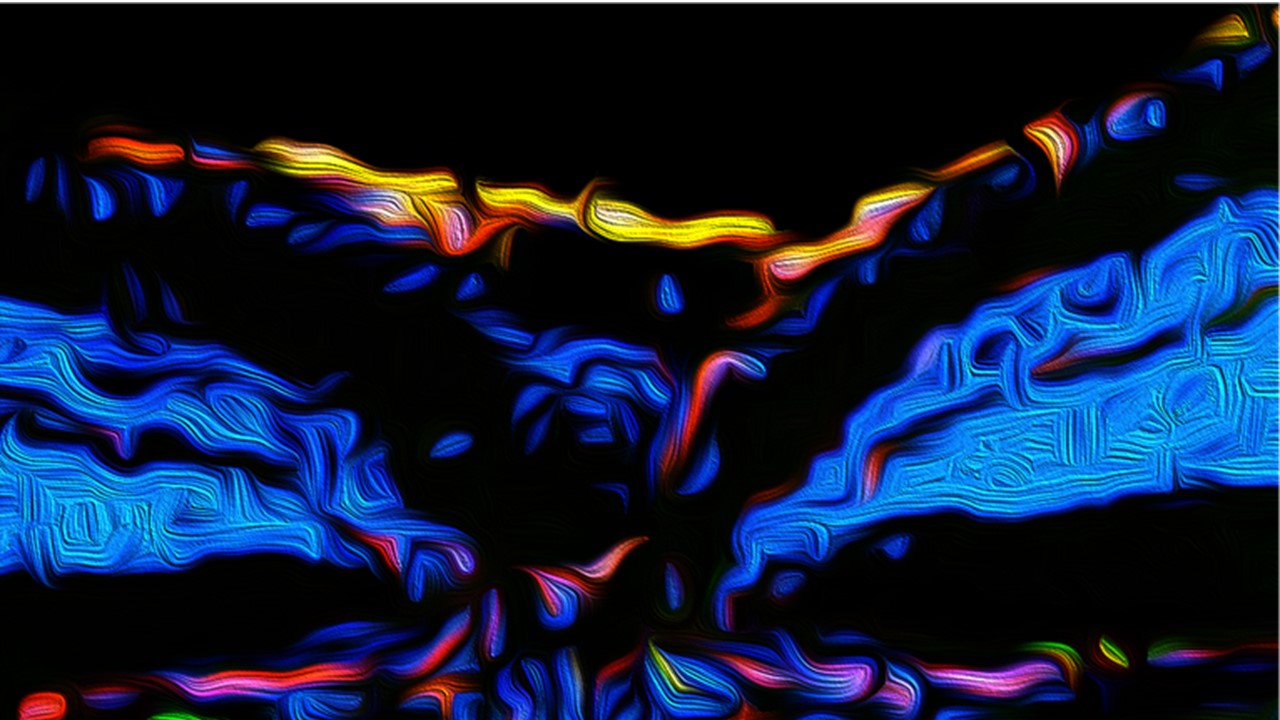

Artistic rendering of choroidal neovascularization: new, damaging blood vessels (highlighted in red) growing from beneath and into the retina of a mouse. This blood vessel growth is typical of patients with wet age-related macular degeneration. Blue highlights the nuclei of cells. Green and yellow highlight expression of ANGPTL4. Credit: Alexander Sodhi, McDonogh School